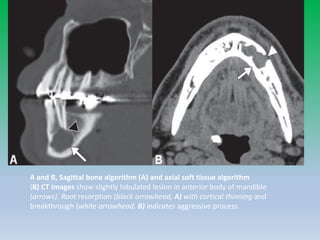

A and B, Sagittal bone algorithm (A) and axial soft tissue algorithm

(B) CT images show slightly lobulated lesion in anterior body of mandible

(arrows). Root resorption (black arrowhead, A) with cortical thinning and

breakthrough (white arrowhead, B) indicates aggressive process.